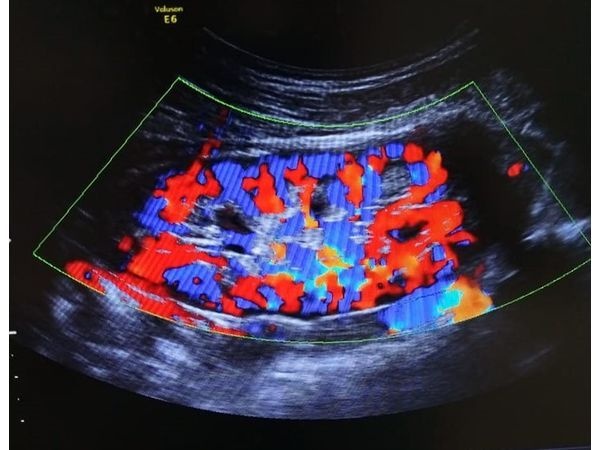

По результатам УЗИ, определяется выпот в обоих тазобедренных суставах, значительно больше в правом. Синовиальная оболочка (тонкая мембрана, которая выстилает суставы) незначительно утолщена. Также видны светлые (гиперэхогенные) включения в толще гиалинового хряща и свободные гиперэхогенные включения в синовиальной жидкости. Предварительный диагноз по УЗИ: артропатия тазобедренных суставов неясной этиологии.

При проведении УЗИ почек видны признаки уплотнения чашечно-лоханочной системы и наличие микрокальцинатов.

По данным контрольного УЗИ, в правом тазобедренном суставе остался незначительный выпот, в левом не обнаружен. Видны единичные кристаллы в области гиалинового хряща и синовиальной жидкости правого тазобедренного сустава.